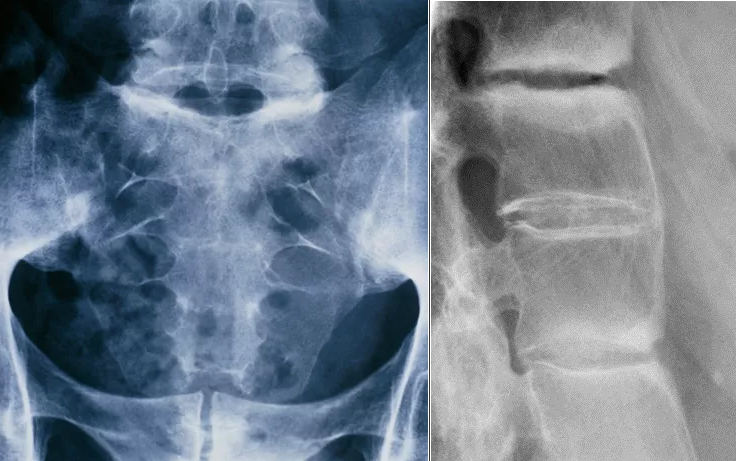

Наиболее ранние рентгенологические изменения – это псевдорасширения суставной щели, причиной которых являются субхондральные эрозии с последующим склерозом или сужением и в конечном итоге – сращением крестцово-подвздошных суставов. Изменения симметричны. Ранними изменениями в позвоночнике являются квадратизация тел позвонков со склерозом углов, пятнистое обызвествление связок, развитие одного или двух синдесмофитов. На поздней стадии позвоночник имеет вид бамбуковой палки с наличием выраженных синдесмофитов и диффузным обызвествлением связок позвоночника, остеопороза; эти изменения развиваются у пациентов в среднем через 10 лет после начала заболевания.

Рисунок 4. Слева: Рентгенограмма таза и крестцового отдела позвоночника (прямая проекция) пациента, страдающего АС, демонстрирует сращения в обоих крестцово-подвздошных суставах. Справа: Рентгенограмма поясничного отдела позвоночника (боковая проекция). Склероз между поясничными позвонками, утрата лордоза и сращение поясничных позвонков, указывающие на прогрессирующий АС.